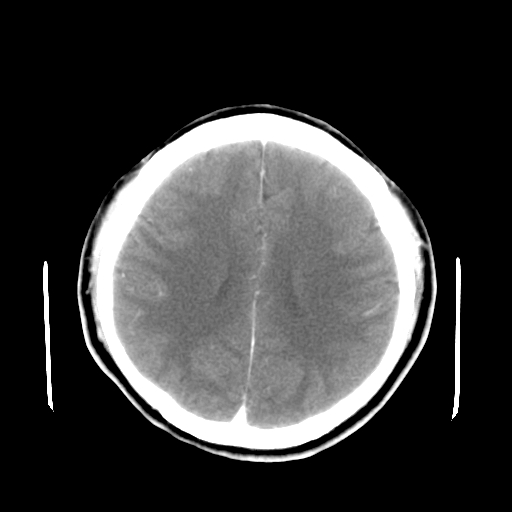

标题: CT16447B:(续)增强扫描图像。

患者今日做ct增强检查,现补传增强扫描图像。

强化并不能解决问题!记得当时我建议mr检查,不一定有事,不过做个放心。

松果体钙癍增大,无其他改变,定不了性

一般认为大于1cm为异常。